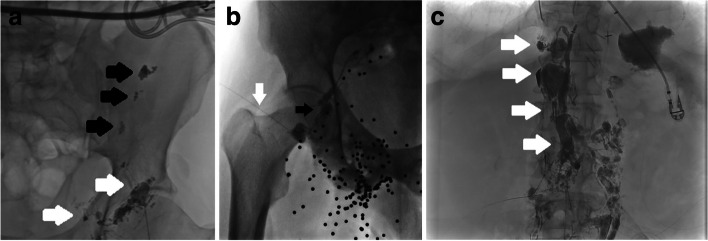

Background: Lymphatic leaks are associated with significant mortality and morbidity. Intranodal lymphangiography (ILAG) involves the direct injection of ethiodised lipid into the hilum of lymph nodes. It is diagnostic procedure that can have therapeutic effects secondary to a local sclerosant effect. The aim of the study is to describe the technical and clinical success of ILAG and adjunctive lymphatic interventions performed as first line interventional techniques for lymphatic leaks refractory to conservative and medical management in a multicentre cohort of patients with symptomatic large volume lymphatic leaks.

Methods: Multicentre retrospective study of all lymphatic interventions performed between 2017-2023 in patients with large volume lymphatic leaks (> 500 ml a day). Intranodal lymphangiography was performed initially with technical success defined as opacification of the lymphatics at the aortic bifurcation and demonstration of lymphatic leak on the index ILAG procedure or immediate post procedural CT was recorded. Lymphatic embolisation was performed with a combination of direct puncture or transvenous cannulation with glue and or coil embolisation of the thoracic duct or leak point and in cases with refractory leak. Clinical success was defined as reduction in drain output to less than 20 mL per 24 h, or no further insensible lymph leak. Time to clinical success after ILAG and adjunctive embolisation was recorded.